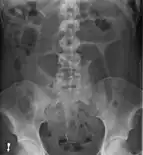

Coffee bean sign in a person with sigmoid volvulus

After taking a thorough history, the diagnosis of colonic volvulus is usually easily included in the differential diagnosis. Abdominal plain x-rays are commonly confirmatory for a volvulus, especially if a "bent inner tube" sign or a "coffee bean" sign are seen. These refer to the shape of the air-filled closed loop of colon which forms the volvulus. Should the diagnosis be in doubt, a barium enema may be used to demonstrate a "bird's beak" at the point where the segment of proximal bowel and distal bowel rotate to form the volvulus.